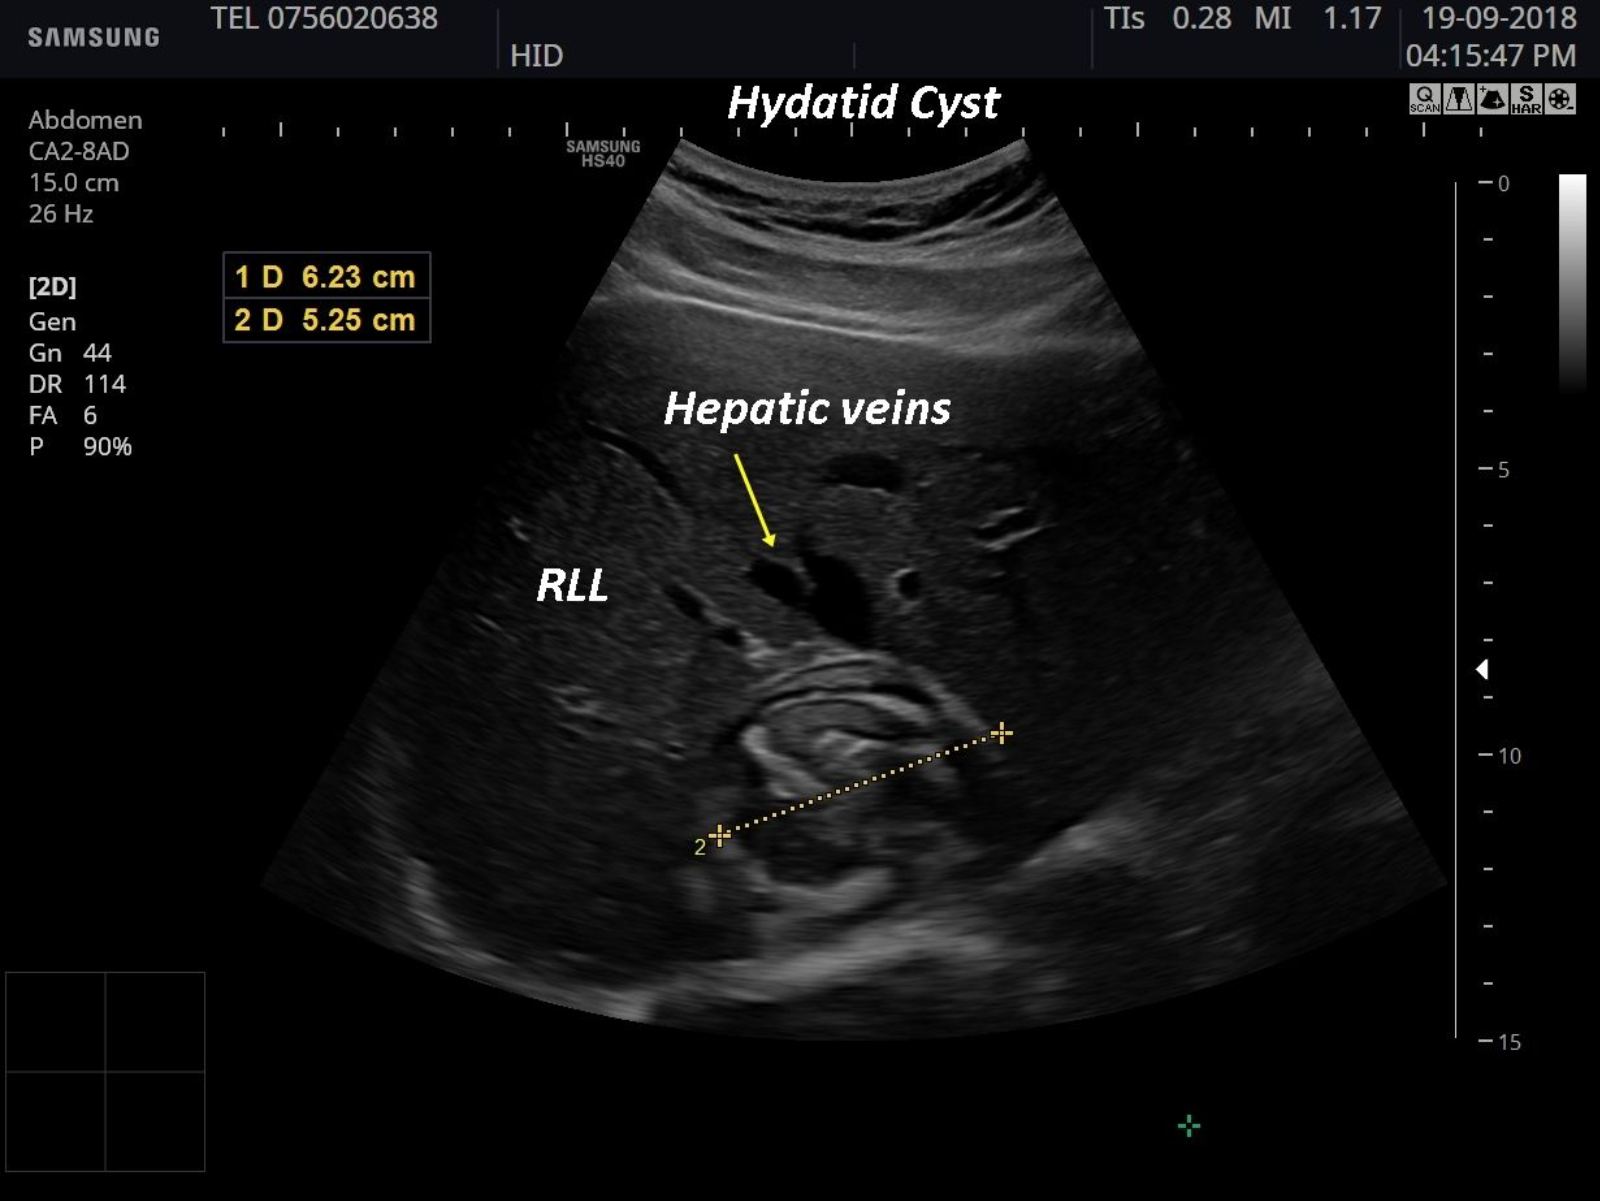

A 72-year-old patient that performed a routine ultrasound scan was diagnosed with a well delineated focal liver lesion in segment VIII. The hyper-heterogeneous aspect, with membranes inside,corresponds toHydatid cyst type IV-according to Gharbi classification